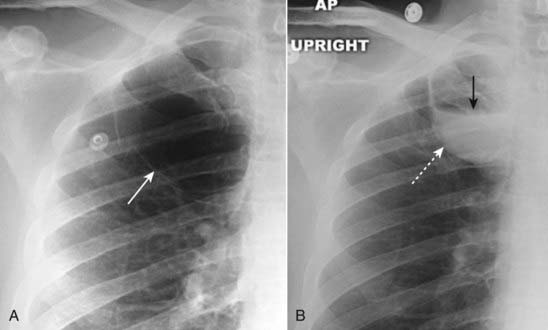

image

Figure 12-20 Hampton hump.

There is a wedge-shaped, peripheral air-space density present (dotted white arrow) associated with filling defects in both the left and right pulmonary arteries (solid white arrows). The wedge-shaped infarct is called a Hampton hump. Without the associated emboli present, the pleural-based airspace disease could have a differential diagnosis that includes pneumonia, lung contusion, or aspiration.

Figure 12-21 Saddle and peripheral pulmonary emboli.

Acute pulmonary emboli appear as partial or complete filling defects centrally located within the contrast-enhanced lumina of the pulmonary arteries. A, A large pulmonary embolus almost completely fills both the left and right pulmonary arteries (solid white and black arrows). This is a saddle embolus. B, A small, central filling defect is seen in a more peripheral pulmonary artery (dotted white arrow). This pulmonary artery seems to be floating disconnected in the lung because the plane of this particular image does not display its connection to the left pulmonary artery.